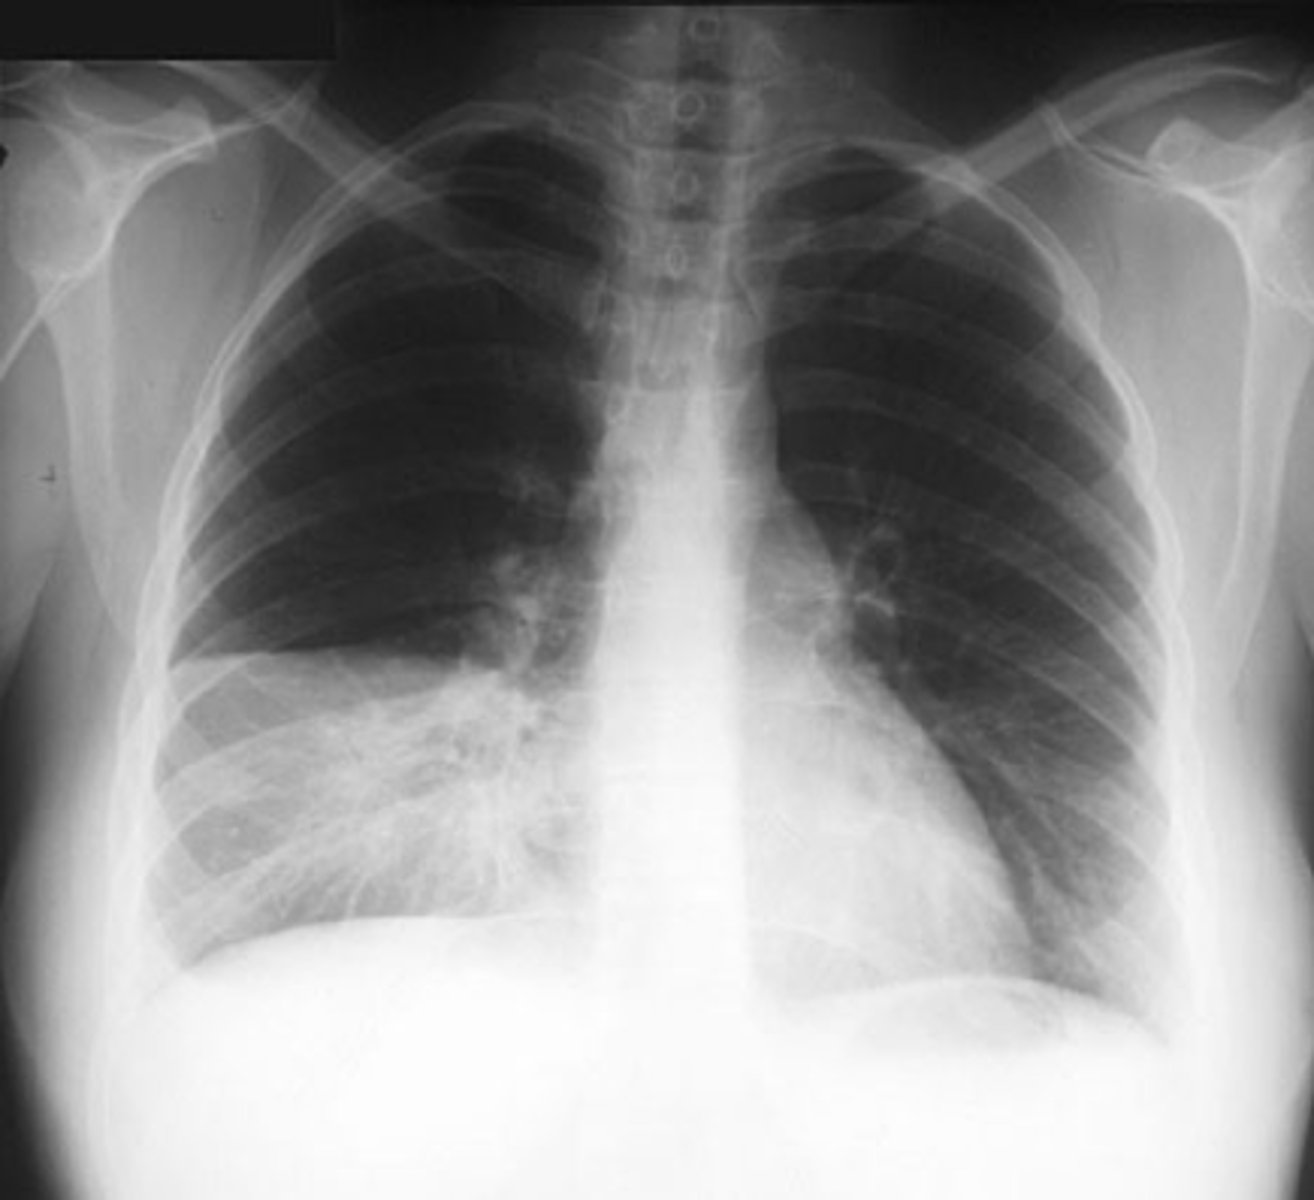

Bilateral pleural effusion